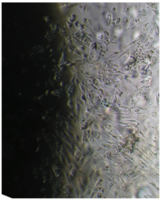

6 серия экспериментов. Образец исследуемого материала (аллогенный ГАП серии «Лиопласт»® массой 2 мг) помещали на дно культуральной чашки, после чего высевали фибробласты в стандартной концентрации.

Щелочной материал резко ухудшает прикрепление фибробластов к дну культуральных чашек (рис. 35) на всей его площади, вместе с тем прикрепившиеся клетки имеют четкие границы, нуклеолемма четко контурирует, цитоплазма гомогенная, без патологической зерностости, вакуолей и включений.

Рис. 35. Выраженная пролиферация, восстановление плотности монослоя.

Фибробласты лишь более распластаны по дну чашки, но это характерно для культуры с малой плотностью.

Вокруг образца через сутки от начала эксперимента клетки не прикрепляются (расстояние от края образца до границы 1,3±0,12 мм).

В последующие дни и до конца наблюдения плотность монослоя  в отдаленной от образца зоне нарастает даже несколько быстрее, чем в контроле, клетки сохраняют обычную для фибробластов в культуре морфологию.

Большое количество слущенных клеток в ростовой среде объясняется ухудшением прикрепления пассированных клеток, а не гибелью уже прикрепившихся (табл. 14).